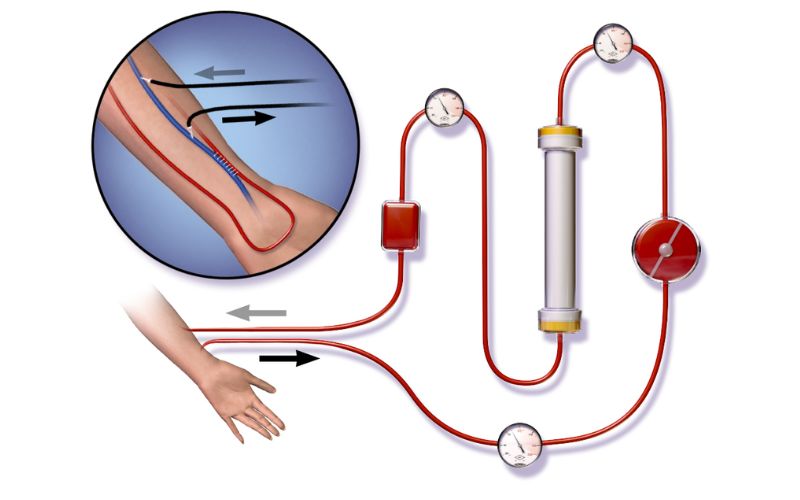

Dialysis

At the forefront of kidney care, our Dialysis and Nephrology services are dedicated to improving the quality of life for patients with kidney diseases.